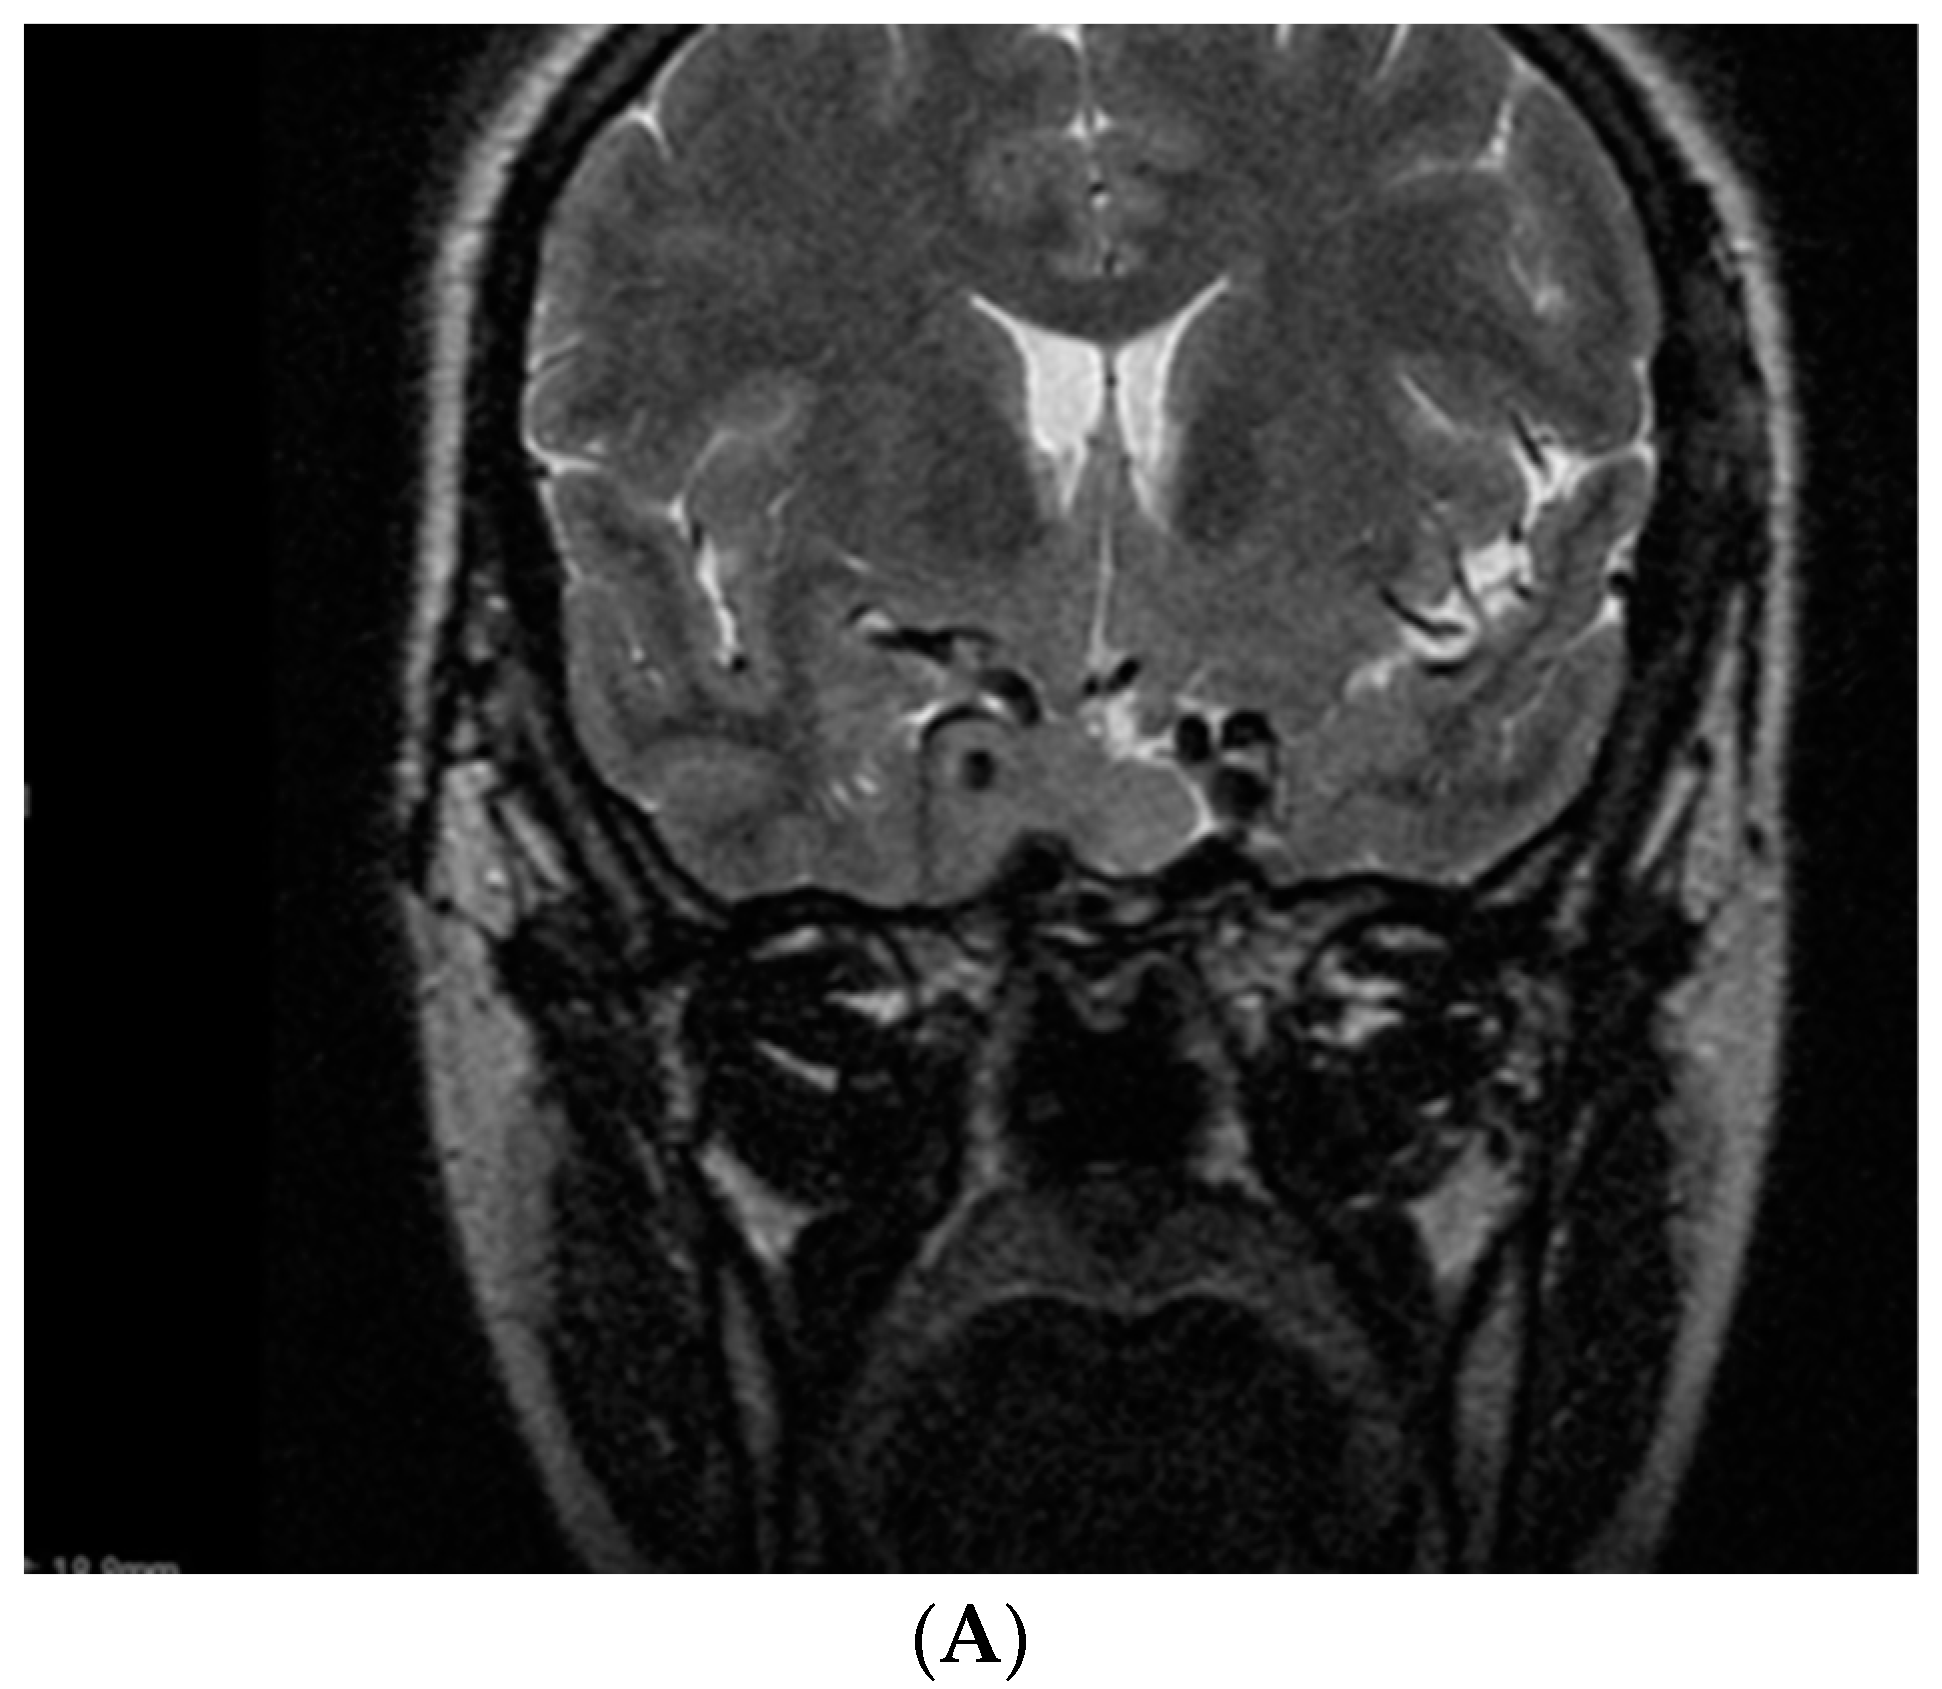

- Kasuki, L.; Neto, L.V.; Takiya, C.M.; Gadelha, M.R. Growth of an aggressive tumor during pregnancy in an acromegalic patient. Endocr. J. 2012, 59, 313–319. [Google Scholar] [CrossRef] [PubMed]

- Dicuonzo, F.; Purciariello, S.; De Marco, A.; Guastamacchia, E.; Triggiani, V. Inoperable Giant Growth Hormone-secreting Pituitary Adenoma: Radiological Aspects, Clinical Management and Pregnancy Outcome. Endocr. Metab. Immune Disord. Drug Targets 2019, 19, 214–220. [Google Scholar] [CrossRef]